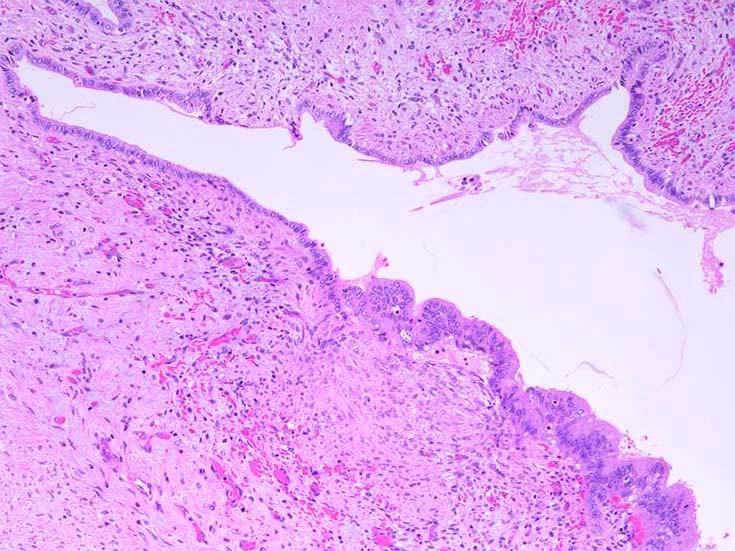

膵上皮内腫瘍性病変 pancreatic intraductal neoplasm(PanIN)*16

Low-grade PanINとhigh-grade PanINの分類

low-grade PanIN

high-grade PanIN

PanINの図譜はJohns Hopkins The Sol Goldman Pancreatic Cancer Research CenterのHome page*19から引用.

1. PanIN-1; PanIN発生の初期段階. 組織学的に, 核異型を伴わない, 核の極性が保たれている.

• telomereの短縮

• KRAS変異

• p16/CDKN2A変異

• Mucin(MUC)発現

2. PanIN-2, PanIN-3;

• TP53の不活化--PanINでのIHCでは機能喪失が,PanIN3のみで観察される. 膵癌発がん過程の遅い段階に出現する事象.

浸潤性膵癌では, 50-75%で不活化.

• SMAD4の不活化--PanIN3の30%で発現陰性化. PanIN-1,2では, SMAD4免疫染色は陽性. 発現の陰性化は後期PanINで発現する重要な異常*20.

浸潤性膵管癌では, 55%で不活化.

• BRCA2(DNA修復に重要な遺伝子)の不活化--PanINではPanIN3に特異的なイベント. germ line変異は浸潤性膵管癌の7~10%に認められる.

• cyclinD1過剰発現--PanIN1ではまれ, PanIN-2では29%, PanIN-3では57%と膵癌発がん過程に伴って頻度が上昇する遺伝子変化.

• COX-2の過剰発現--悪性腫瘍では, 細胞増殖, 生存, 浸潤および, 血管新生に関与. 正常膵管,PanIN-1では発現が低く, PanIN2から過剰発現頻度が高くなる.